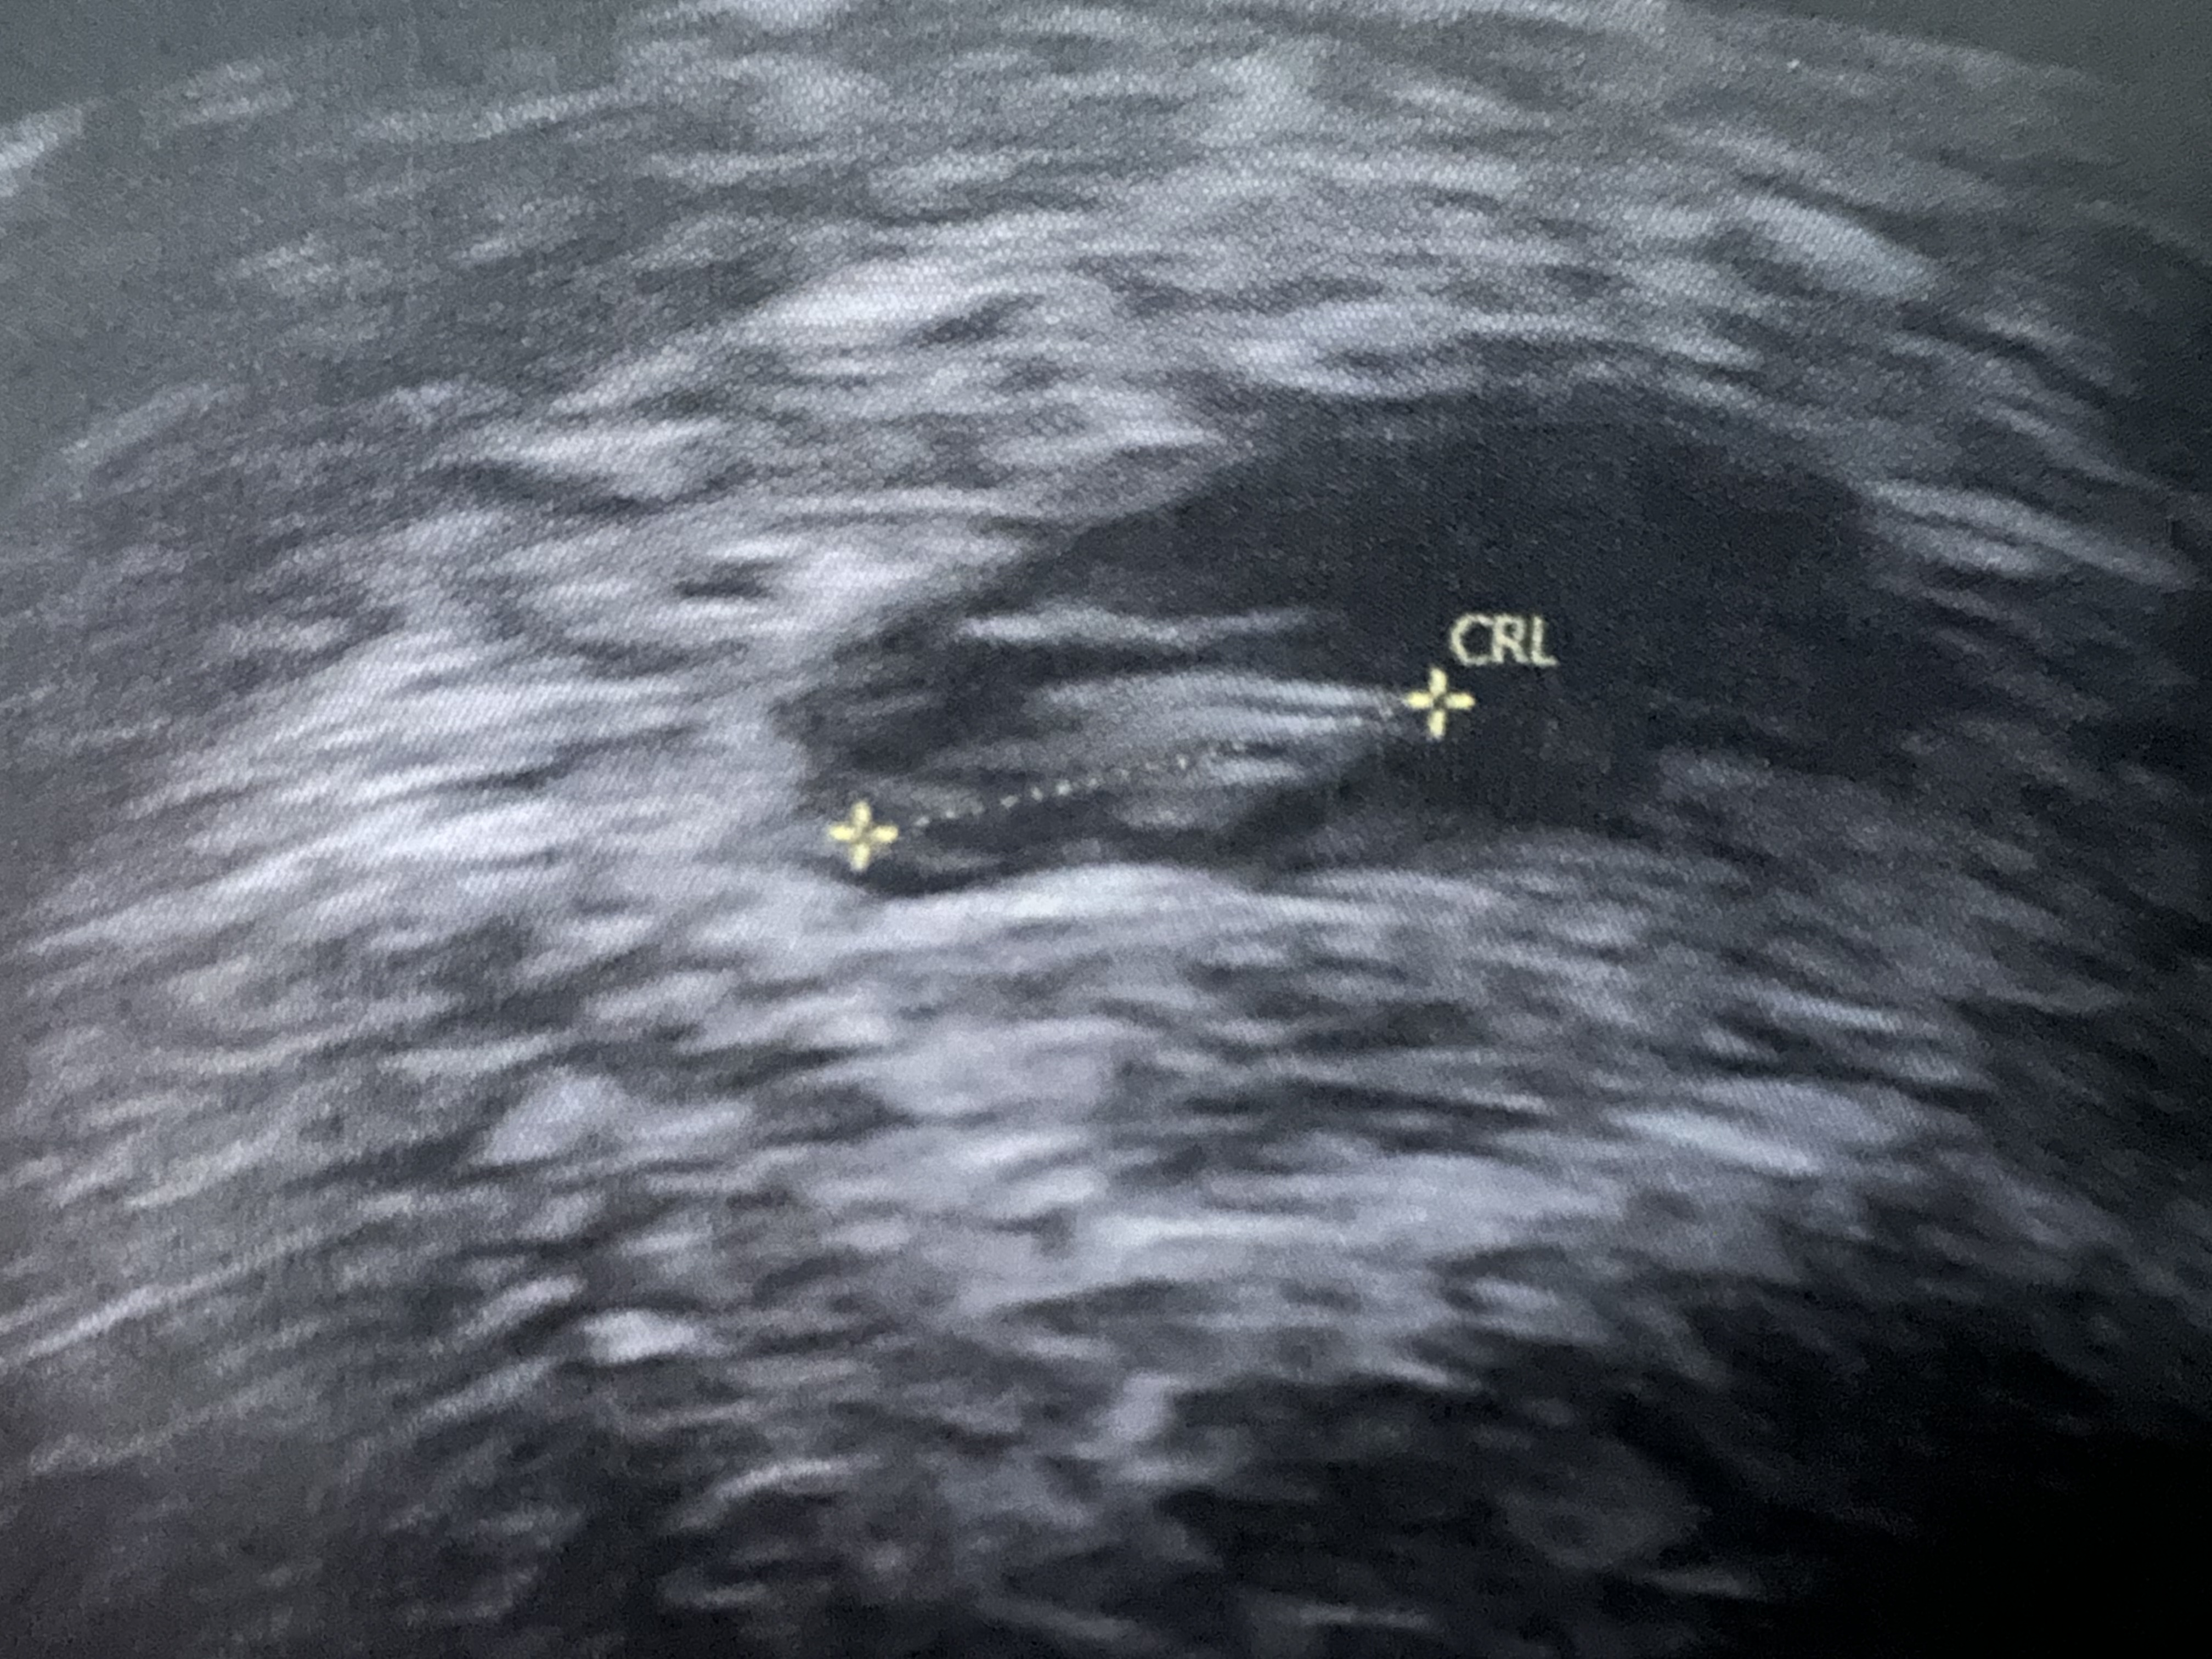

Ultralyd er ferdig, og det lille, fine hjertet slo fortsatt fintFor en lykke. En centimeter lykke